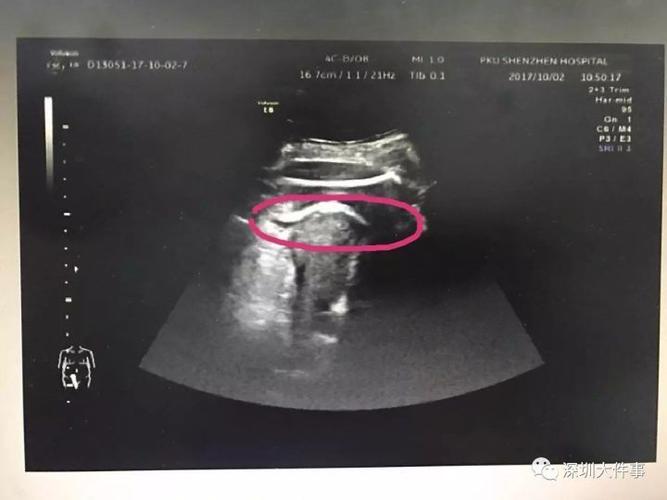

胎儿一脚踢妈妈破子宫b超照吓到医生

"虽然没有找到子宫的破裂口,但通过b超可以看到,在孕妇腹部最疼的地方